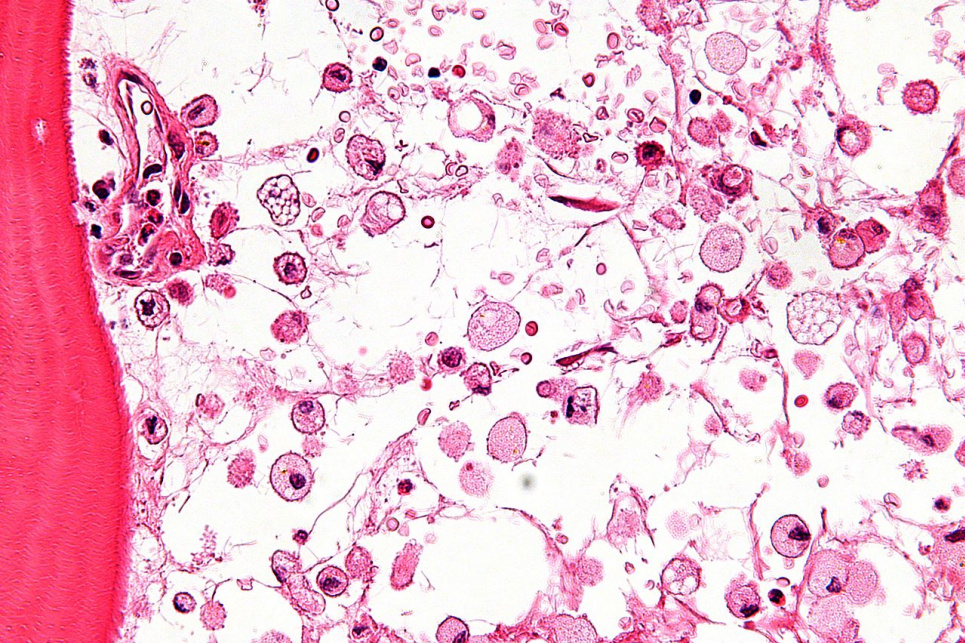

Фото: Wikimedia.org26 липня — не просто дата в календарі, а важливий день для тисяч людей по всьому світу. Цього дня відзначається Міжнародний день обізнаності про хворобу Гоше, присвячений рідкісному генетичному захворюванню, яке потребує особливої уваги та розуміння.

Хвороба Гоше — це спадкове метаболічне захворювання, що належить до групи лізосомальних хвороб накопичення. Вона виникає через дефіцит ферменту, який відповідає за розщеплення жирової речовини. Коли цього ферменту недостатньо, глюкоцереброзид накопичується в клітинах різних органів, найчастіше в селезінці, печінці, кістковому мозку, а іноді й у нервовій системі. Це призводить до збільшення органів, болю в кістках, анемії, підвищеної втомлюваності та інших серйозних проблем зі здоров'ям.